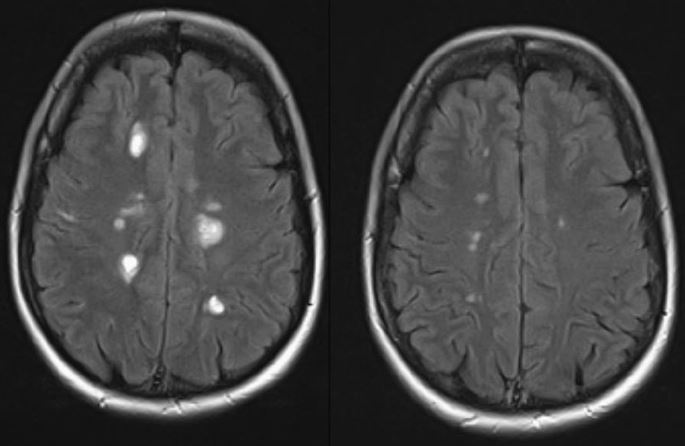

That's why I decided to share a (as I find especially beautiful) MRI comparison (09/2017 /-09/2018).

The lesions have been very good, and I think that's especially because they were fresh when I started with the CP. Honestly, I have to say that during the relapse (about 2 months before the official cp start) I already took 40.000 IU Vitamin D.